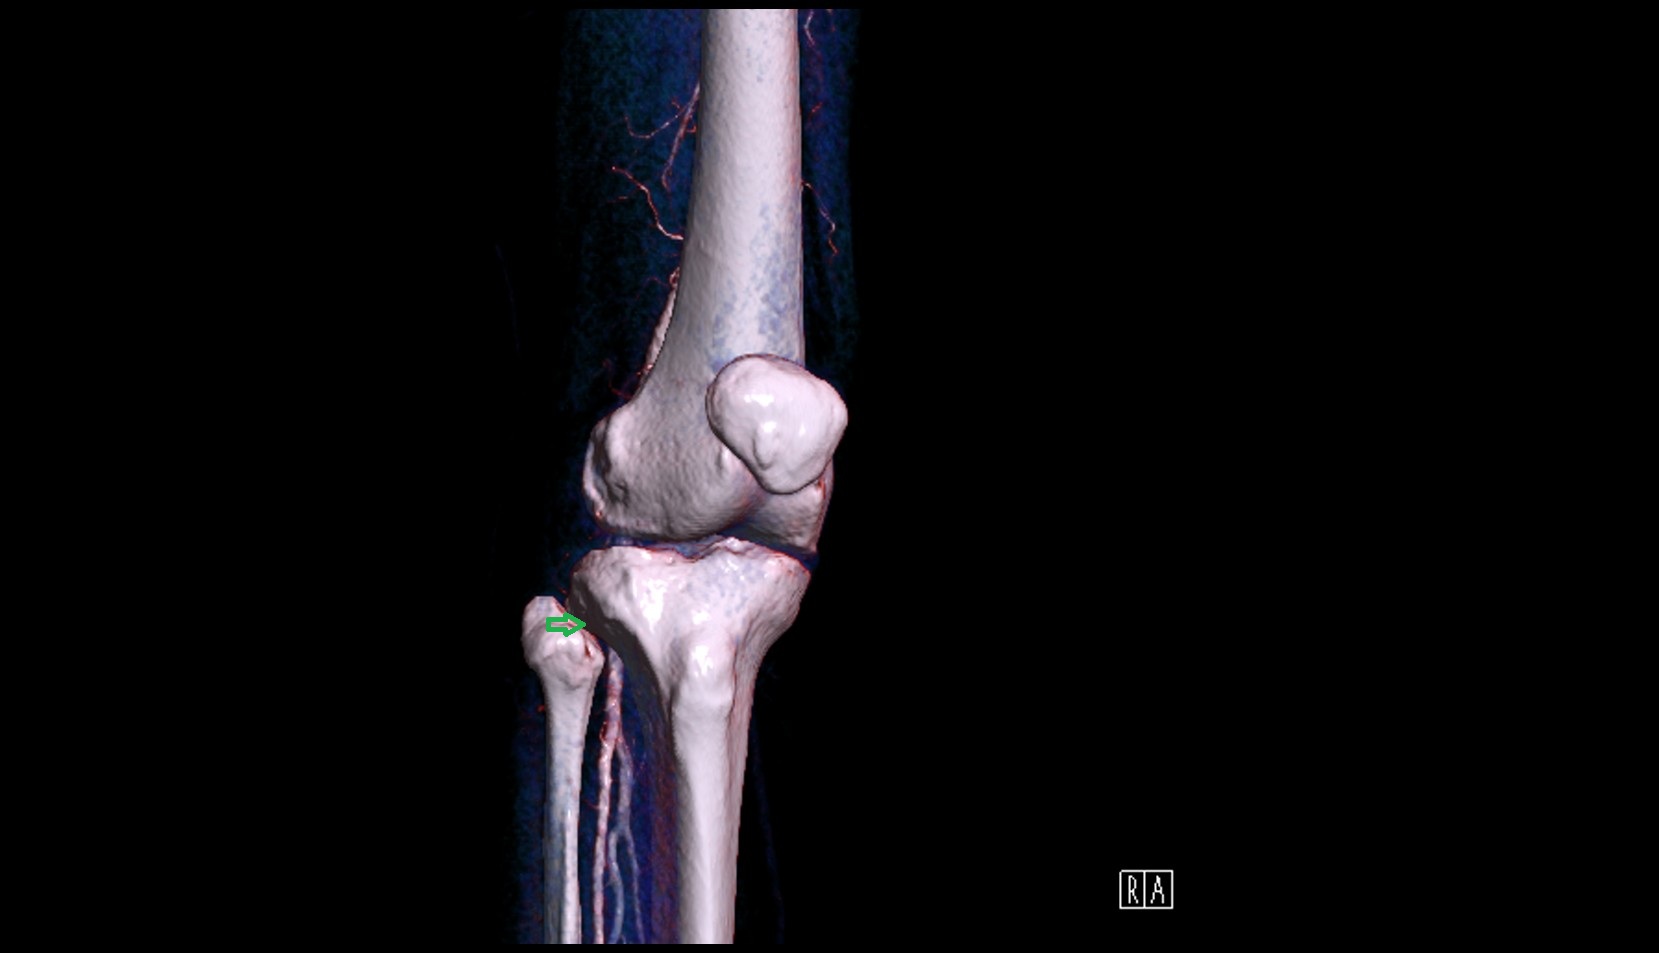

- Elbow joint

- Head of radius

- Olecranon

- Coronoid process of ulna

- Radius

- Ulna